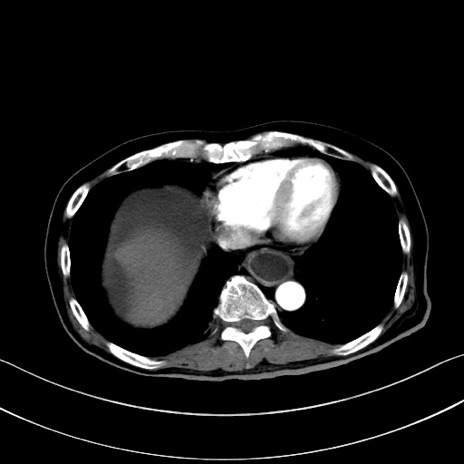

症例28(横断像)

【症例】60歳代男性

【主訴】嘔吐

【現病歴】胃癌にて胃全摘後。食思不振が悪化し、夜中に嘔吐することがある。

【既往歴】胃癌、胃全摘、脾摘、胆摘後

【データ】WBC 5900、CRP 10.56